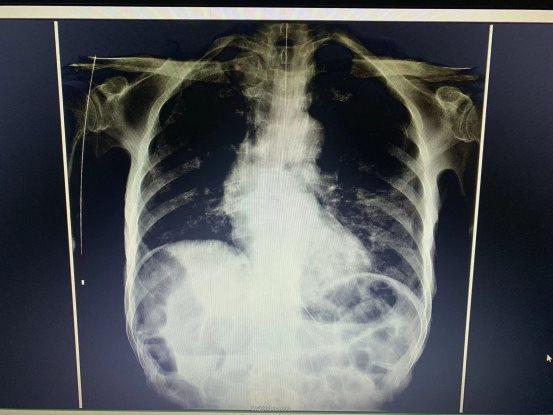

该患者为老年男性,因喉癌术后,长期胃肠营养管营养支持,一天前,营养管不慎脱落,无法进食水。患者在家属的陪同下来4118ccom云顶胃镜室,准备行内镜引导下空肠营养管植入术。陈久红主任首先经鼻置入空肠营养管,由于喉癌术后,咽部解剖结构改变,结合局部疤痕组织增生,营养管难以顺利进入食管,遂在胃镜直视下,反复多次调整营养管方向,后顺利进入食管,因胃镜无法进入食管故无法判断营养管置入的位置。陈主任亲自陪同患者到放射科,X线透视,提示营养管位置准确。